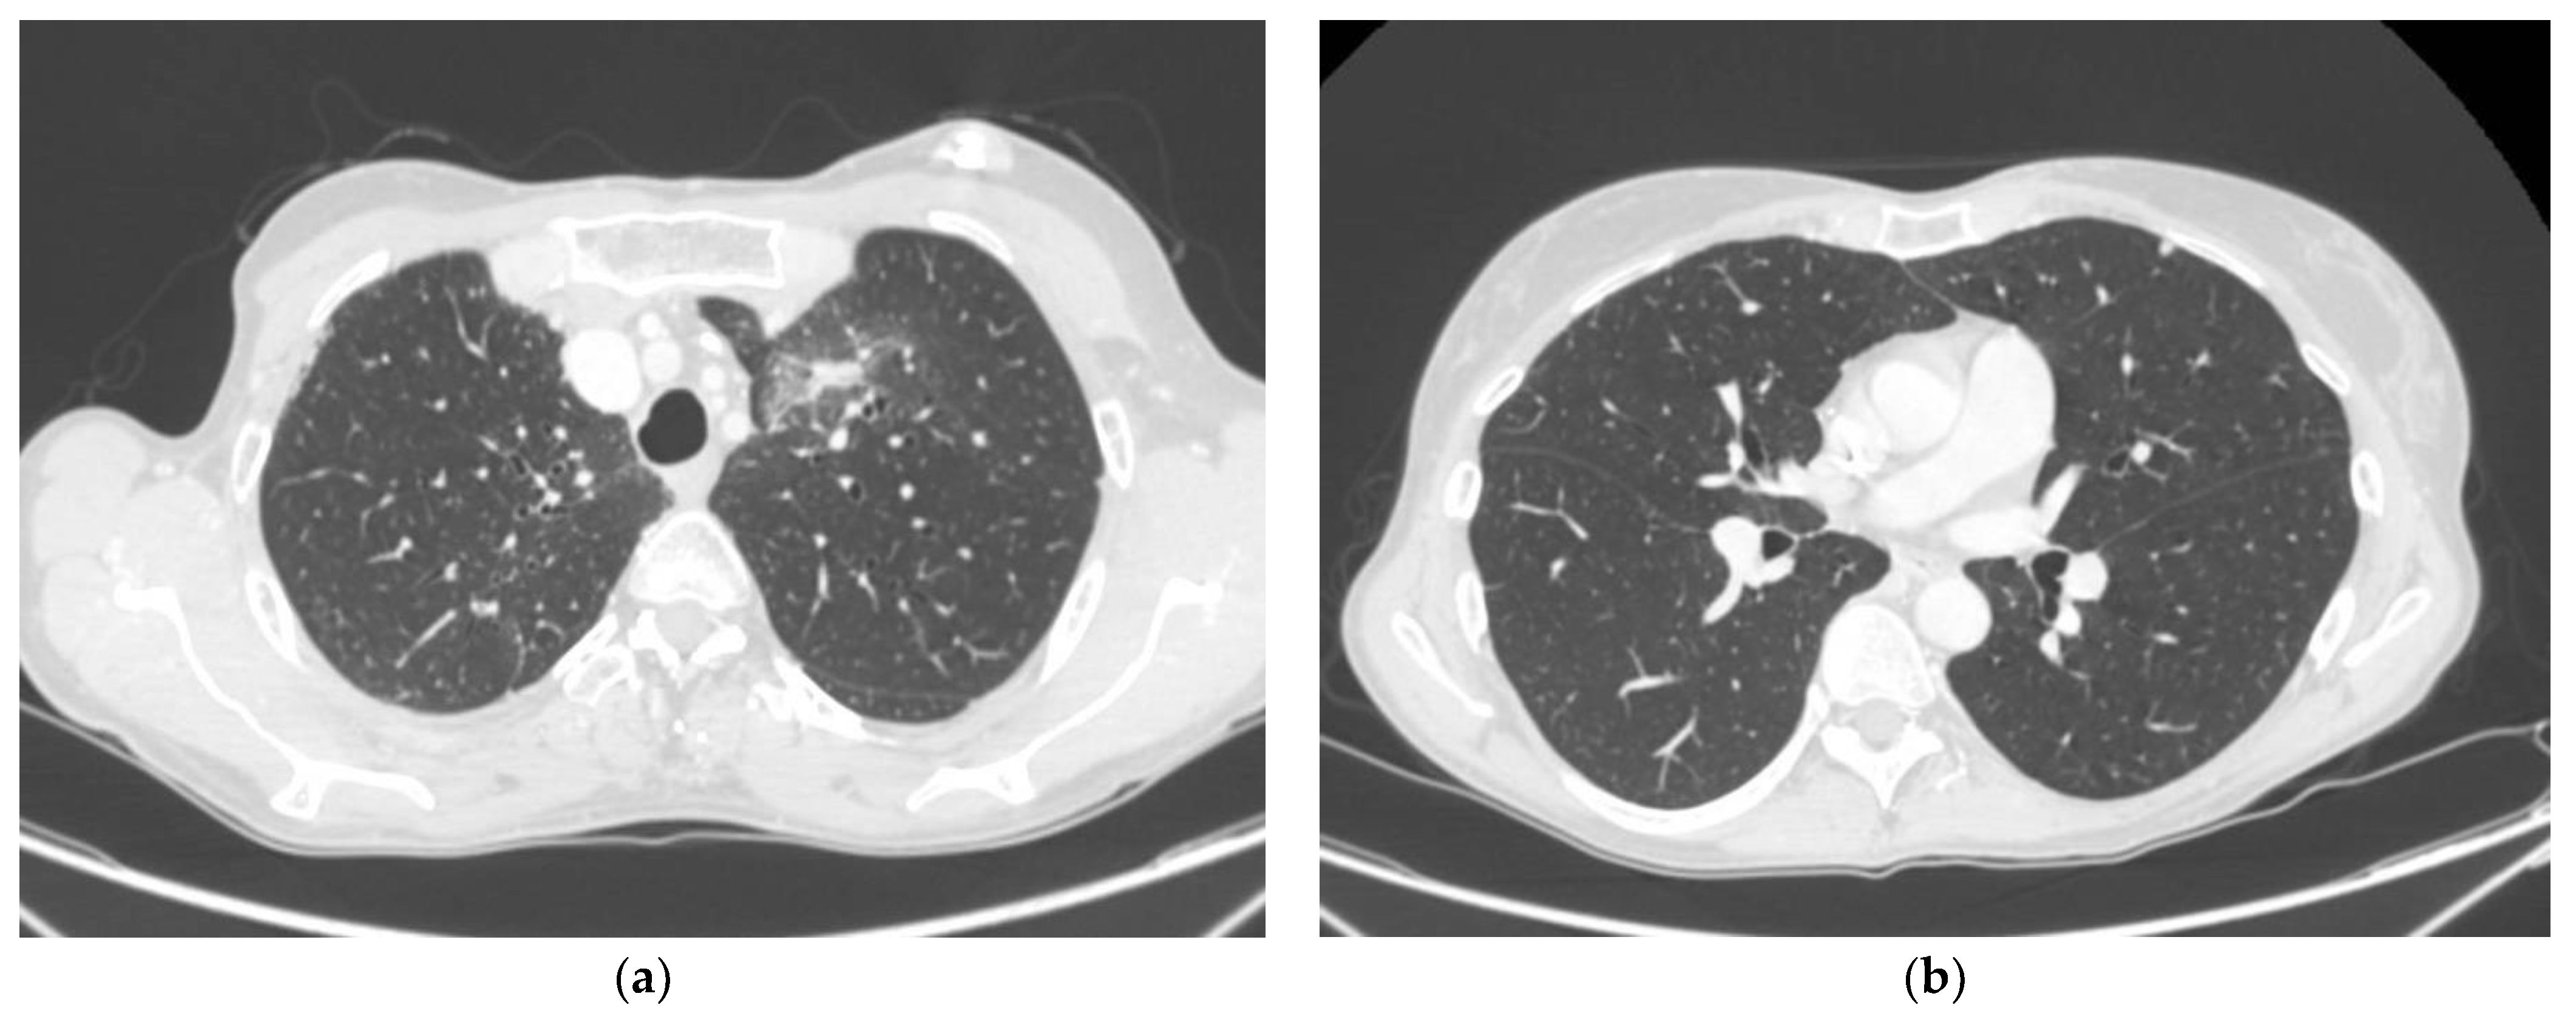

| Lung | 3 pts (5.1%) | |

| Lung RT treatments | SBRT 50 Gy in 5 fr | 3 pts (100%) |

| BED schedule analysis(For every analysis, patients were grouped according to dichotomous categories, resulting in more than one category) | RT with schedules ≥100 Gy for α/β = 10 | 9 pts |

| RT with schedules ≥100 Gy for α/β = 4 | 18 pts | |

| RT with schedules ≥75 Gy for α/β = 10 | 14 pts | |

| RT with schedules ≥75 Gy for α/β = 4 | 44 pts |